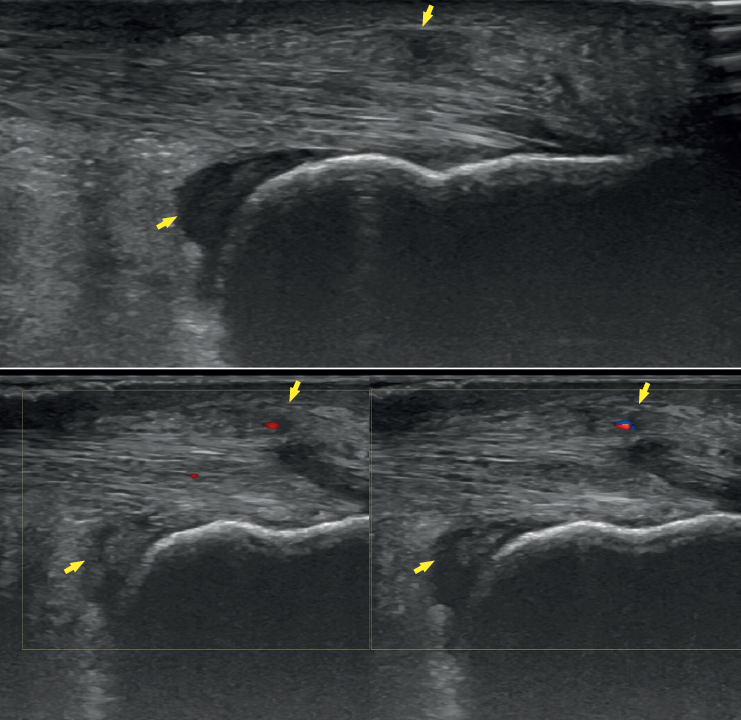

Ultrasound allows us to identify inflammatory signs in both bursae, tendon lesions and bone exostosis. Tendon degeneration is characterised by poorer echogenicity (a lower mean value on the scale of greys), due to the lesser organisation and altered composition of the tendon microstructure(21). Doppler ultrasound in turn allows us to assess neovascularisation zones (Figure 4). Ultrasound offers dynamic exploration and is operator-dependent.

Figure 4. Ultrasound exploration. Retrocalcaneal bursitis and signs of tendinopathy (yellow arrows). Doppler ultrasound allows the identification of tendon hypervascularisation areas.